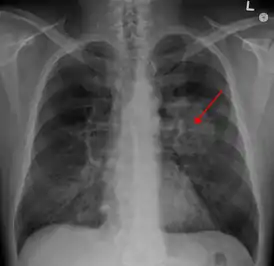

![]() Рентгенограмма грудной клетки, демонстрирующая опухоль в лёгких | |

Рентгенологическая диагностика

Рентгенологическое исследование является одним из основных методов диагностики опухолей лёгкого и позволяет своевременно обнаружить его у 80 % больных. В качестве скринингового метода используется флюорография, которая обычно проводится во время профилактических медосмотров. При выявлении изменений (солитарный лёгочный узел, ателектаз и т. д.) на флюорограмме или при наличии клинических показаний применяют рентгенографию в двух проекциях и компьютерную томографию. Кроме того, компьютерная томография является наиболее информативным методом диагностики метастазов в других органах.